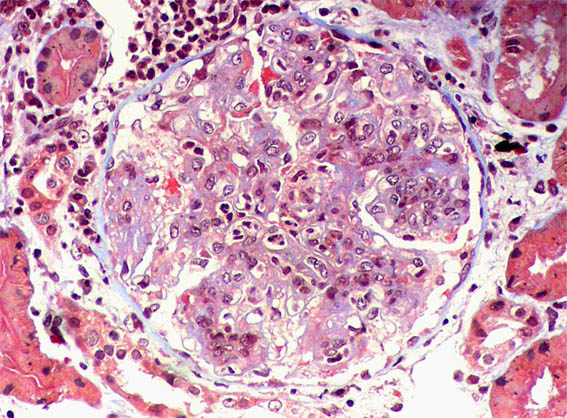

Figure 3. H&E, X400.